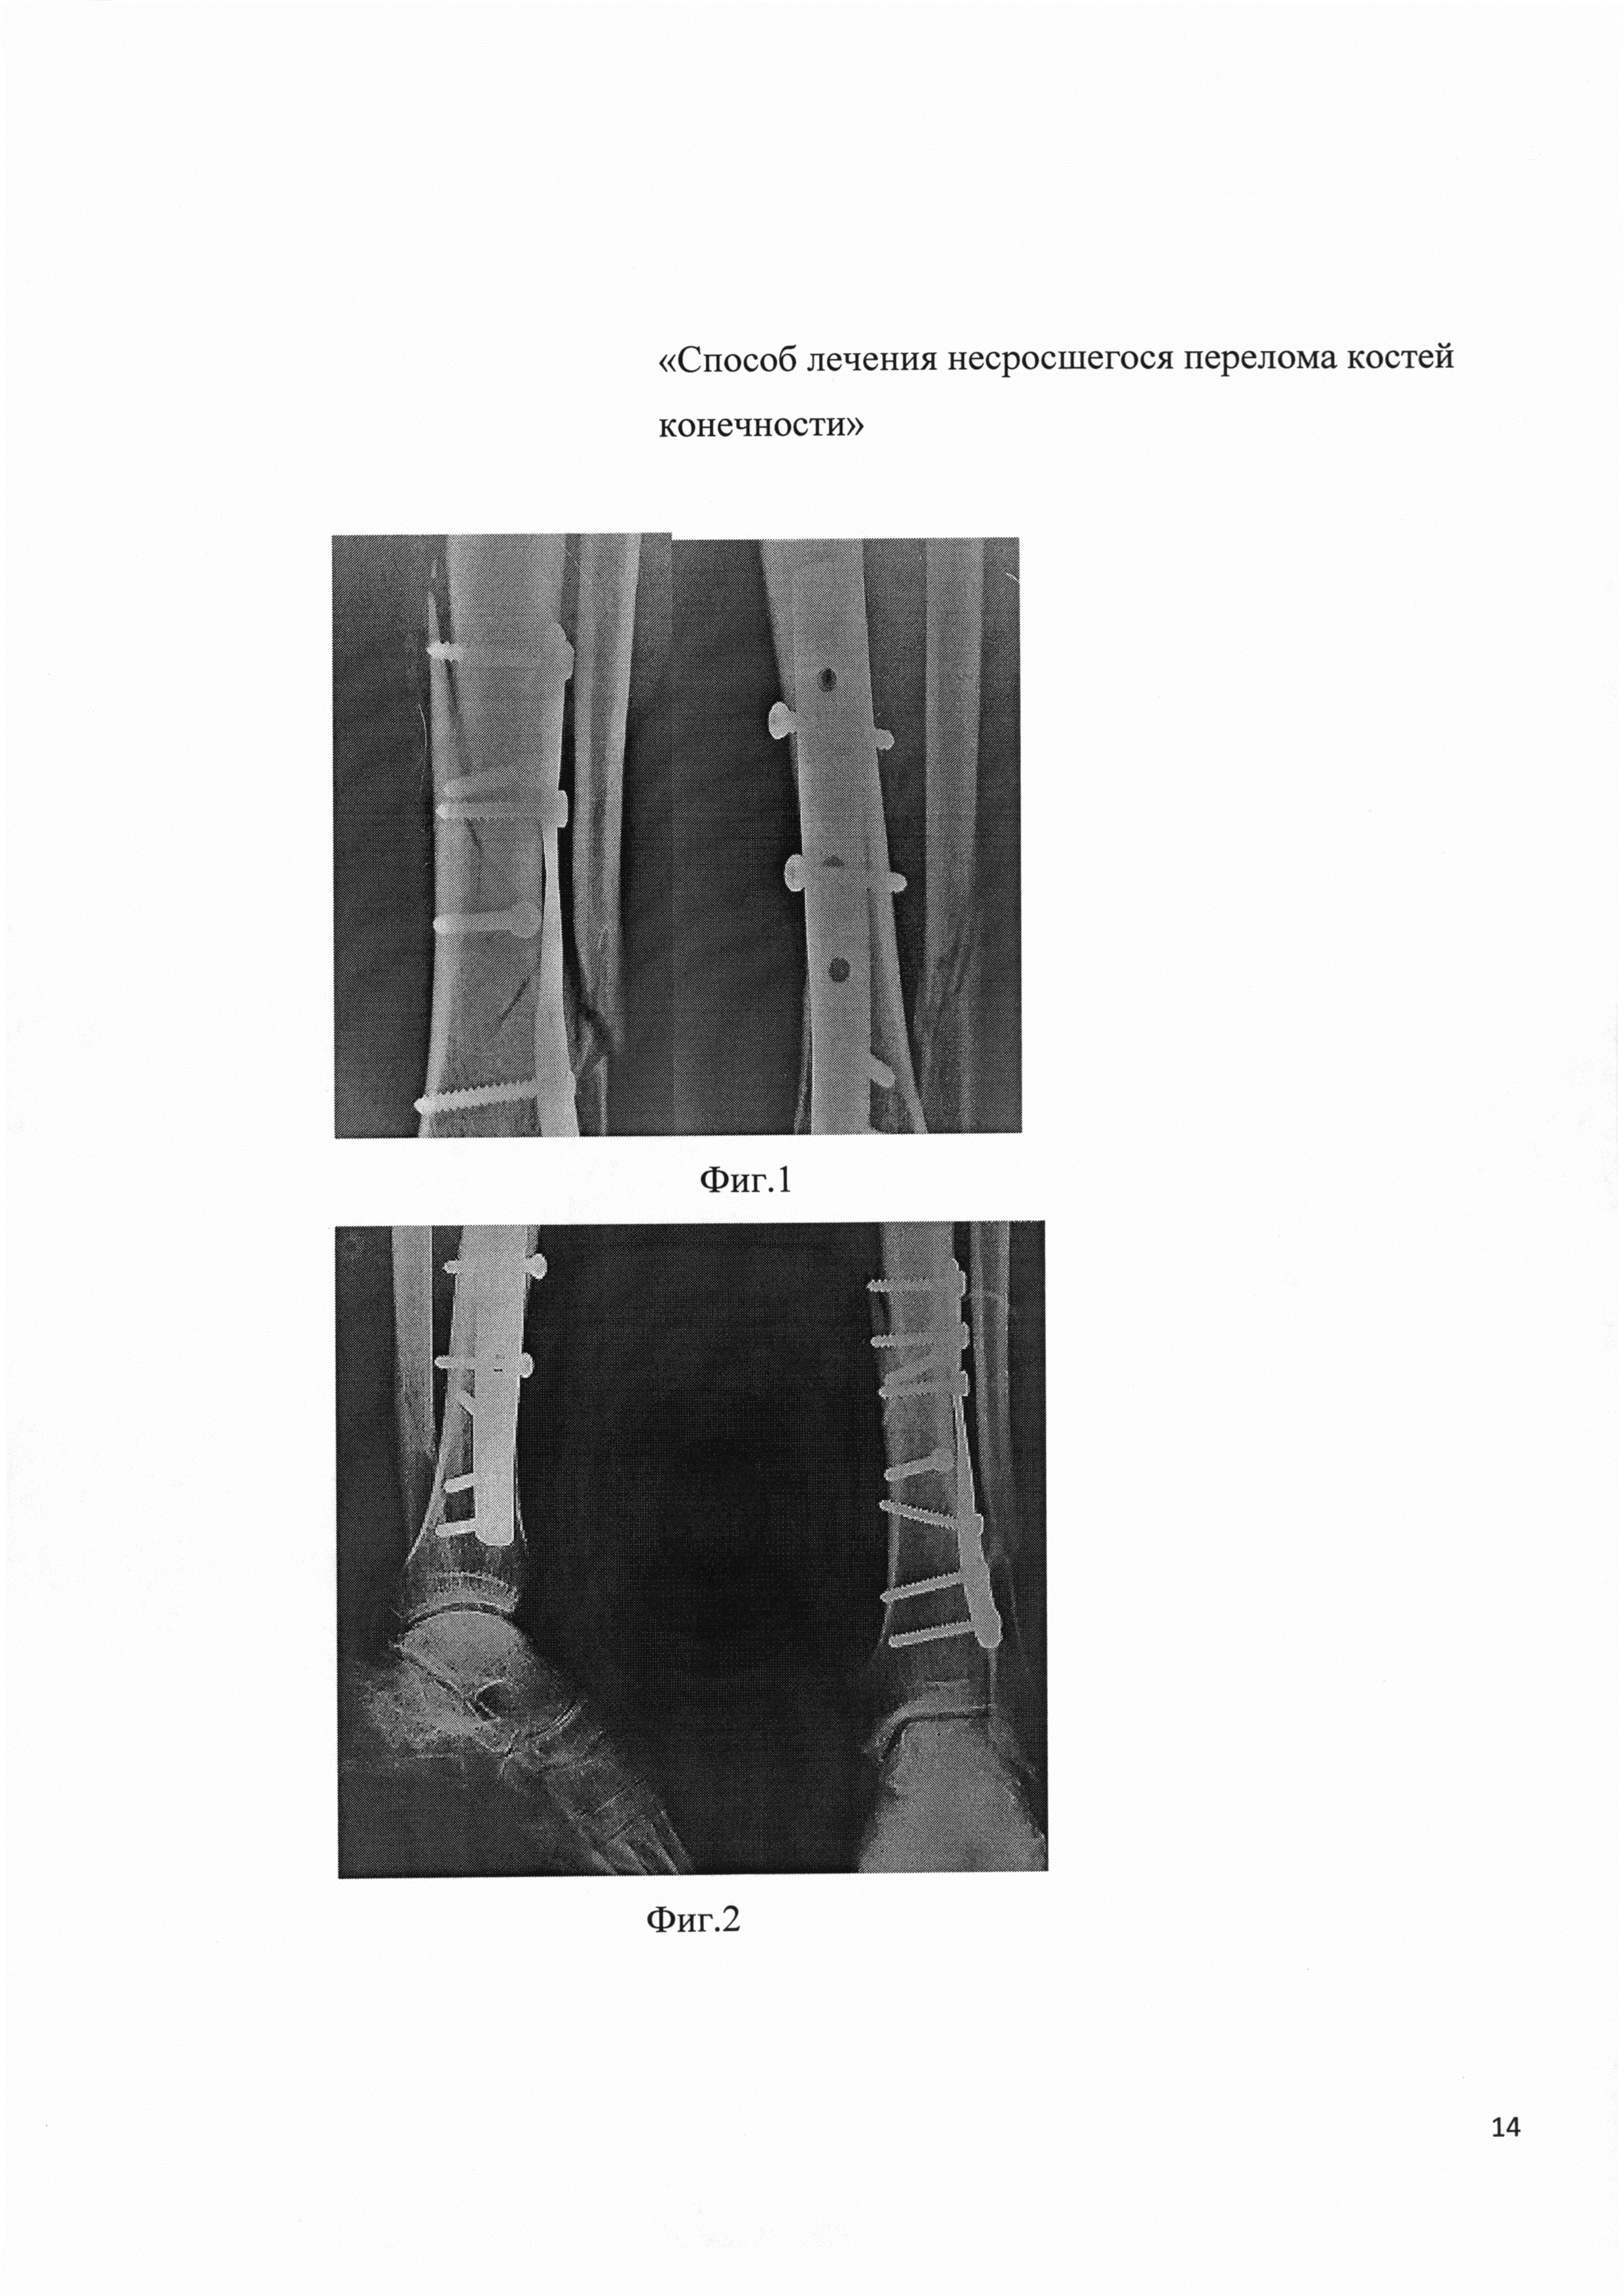

Срастающийся перелом мкб 114 фото